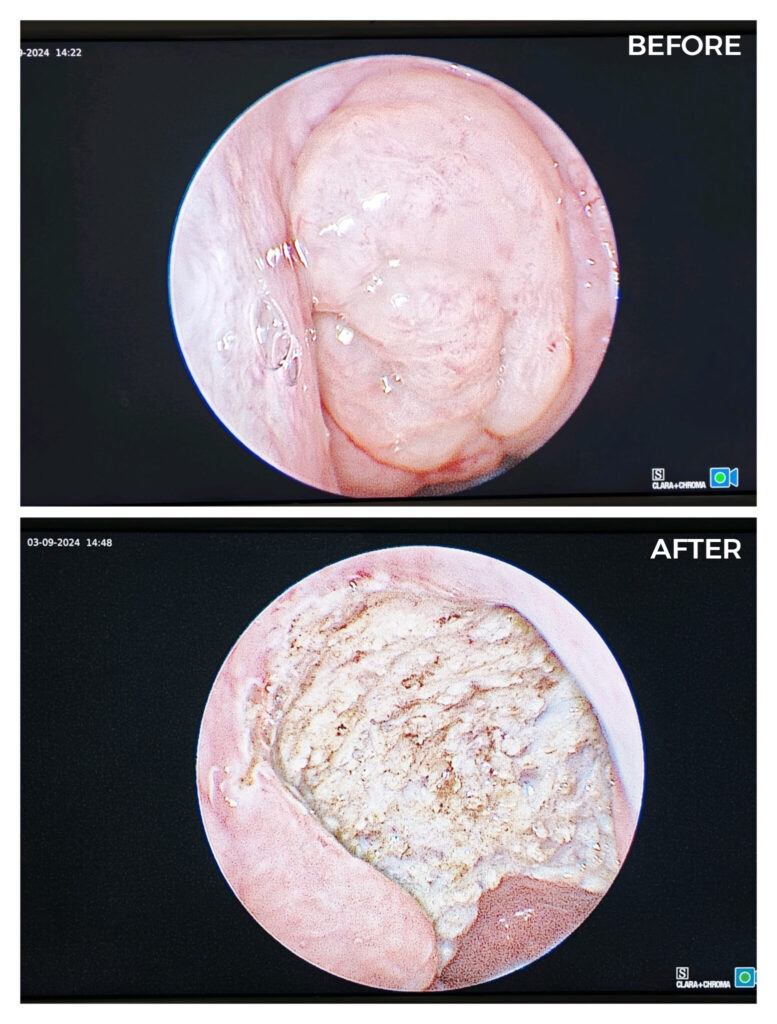

Endoscopic Coblation Adenoidectomy

Medtronic BiZact assisted bloodless Tonsillectomy

Endoscopic Septoturbinoplasty